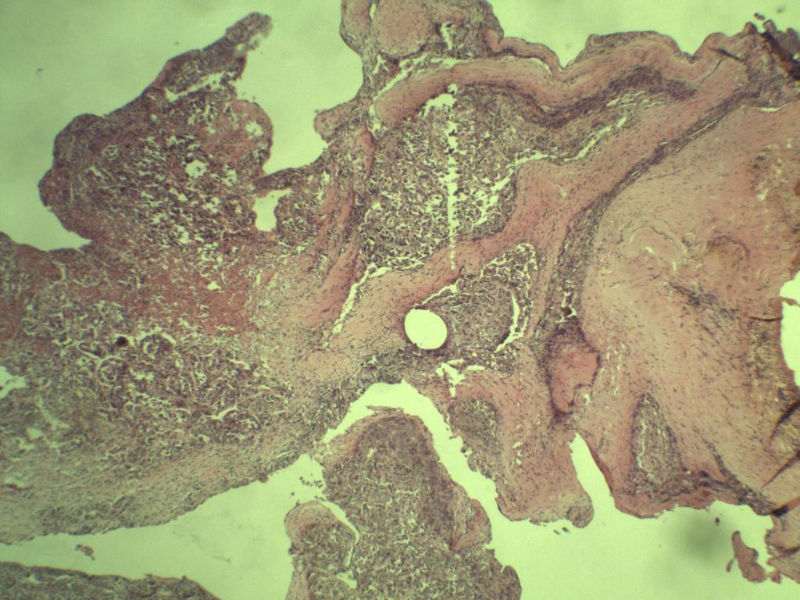

女 70岁 右颈部 头皮 多发皮下结节      取颈部部分结节送检 灰白小组织 1 块,直径 0.4 cm。 请问这个是什么?

肿瘤细胞大,上皮样,核空泡状,核仁明显,胞质嗜酸性或透明。

考虑:恶性黑色素瘤?

近心型上皮样肉瘤?

软组织透明细胞肉瘤?

上皮样多形性脂肪肉瘤?

等免疫组化标记!

此片染色欠佳,取材或切面也有问题,加大了诊断的难度,恶黑确实需要考虑,但其他一些转移癌也需要排除,比如肺癌之类的,还是期待免疫组化!